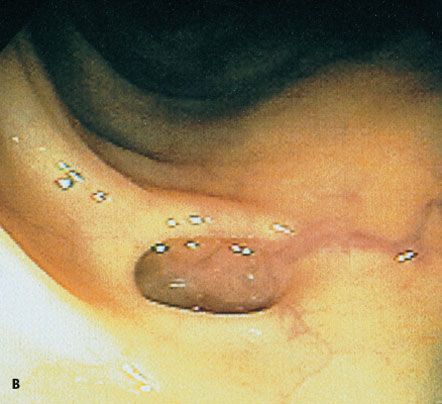

A previously healthy man had 10 to 15 episodes daily of small-volume bloody diarrhea with intermittent paraumbilical pain. A colonoscopy showed diffuse ulceration with loss of vascularity and mucosal surfaces from the rectum to the cecum. Distinct, irregular, raised areas of normal-appearing mucosa were noted among the areas of friability, fibrous stranding, and ulceration (arrow). The patient had ulcerative colitis with pseudopolyps.

Image courtesy of Chad M. Sisk, DO.